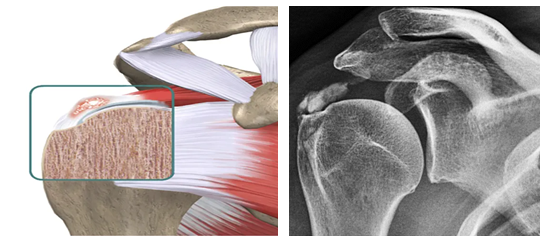

A tendinite calcária é quando cristais de cálcio se formam dentro dos tendões do ombro. Isso pode causar muita dor, especialmente na hora de levantar o braço. Não é algo incomum, muitas pessoas passam por isso, mas a boa notícia é que tem tratamento. O objetivo principal é diminuir a inflamação e aliviar essa dor chata que limita seus movimentos.

Sabe aquela dorzinha chata no ombro que parece não ir embora? Pois é, muitas vezes ela pode ser um depósito de cálcio. Isso acontece quando o cálcio, que normalmente está dissolvido, começa a se formar em pequenos cristais dentro dos tendões do ombro. Essa calcificação pode irritar o tendão e gerar bastante incômodo, especialmente com os movimentos.

Depois dessa conversa inicial, o próximo passo é o exame físico. O médico vai movimentar seu braço em diferentes posições para ver quais movimentos desencadeiam a dor e onde ela é mais intensa. Ele pode pressionar certas áreas do ombro também. E para ter certeza absoluta, a radiografia (o raio-X) é quase sempre o exame principal. É nessa imagem que as famosas calcificações no tendão aparecem bem visíveis, confirmando o diagnóstico. Às vezes, se houver alguma dúvida, pode ser solicitado um ultrassom, que mostra os tecidos moles com mais detalhes.

A confirmação vem com a imagem certa, mostrando aquelas calcificações que causam a inflamação e a dor no ombro. É importante não se desesperar ao ouvir o diagnóstico. O tratamento para a dor no ombro por tendinite calcária existe e pode trazer muito alívio. Vamos combinar, ninguém merece ficar com dor, né? Buscar ajuda médica logo no início faz toda a diferença.